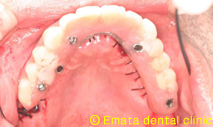

患者様は元々入れ歯をつかったことがありません。上顎6歯が歯周病が進行し残念ですがすべて抜歯です。年齢的(60歳)にも仕事上からも、総入れ歯は絶対いやだということで、All-on-4によりその日で固定式の仮歯を入れる手術をおこないました。

All-on-4は4本ではないかとおもいますが、骨の状態や対合歯が自分の歯なのでより確実性をもたせたいため5本で立ち上げ、2本はスリープさせました。

麻酔専門医の先生が静脈内鎮静法を行っていますので患者さんは半分寝ているうちに手術が終わってしまいます。

仮歯までいれるのに半日かかりましたが、患者様には大変喜んでいただきました。

治療後